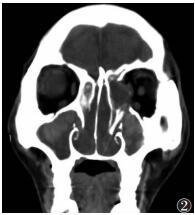

骨质增生14例,其中内侧壁受累4例,外侧壁10例,表现为窦壁较均匀增厚,窦腔轻度缩小。骨质破坏7例(图 2,3),其中内侧壁受累5例,外侧壁受累2例,表现为骨质吸收、缺损,周围有软组织肿块。

| 图 2 男,51岁,真菌性上颌窦炎。双侧上颌窦、筛窦及鼻腔内软组织影充填,其内有斑片状高密度影,鼻道闭塞,左侧眼眶内壁破坏、中断 |

2.2.4 病变周围情况单侧病变同时累及同侧筛窦10例,累及同侧鼻腔7例(图 2)。双侧病变均同时累及鼻腔,其中双侧9例,单侧2例;同时累及双侧筛窦6例,单侧筛窦3例。窦腔骨壁增厚25例,骨质破坏7例,其中累及内侧壁5例,外侧壁2例。筛窦骨质破坏2例。上颌窦窦口扩大9例。累及筛窦者为筛窦气房密度增高,窦腔闭塞,其内见斑片状高密度影。累及鼻腔者鼻腔内软组织影充填,密度不均,其内见多发斑片状、结节状及团块状略高密度影,鼻道闭塞。累及鼻后孔4例。